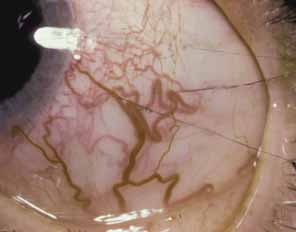

In the second condition, anomalous superficial iris vessels wander irregularly over the iris surface with an often distorted pupil (Fig. 4). The iris surface has a whorled appearance and the anterior iris stroma is often hypoplastic. These vascular anomalies differ from the normal exposure of radial iris vessels seen in lightly pigmented eyes. Anomalous iris vessels are seen most frequently in eyes that present with glaucoma and cloudy corneas at birth, and are not associated with any particular syndrome. It is unclear whether they represent an earlier onset of primary congenital glaucoma or an entirely different syndrome. They do indicate a more severe malformation of the anterior segment and a grave prognosis, with such cases requiring multiple surgeries.

Fig. 4 Anomalous iris vessels. Vessels course irregularly over the iris surface. On the right, small vessels are seen crossing the pupillary margin. The pupil is distorted at the 10 o'clock position. Radial iris fibers are curved and irregularly arranged.